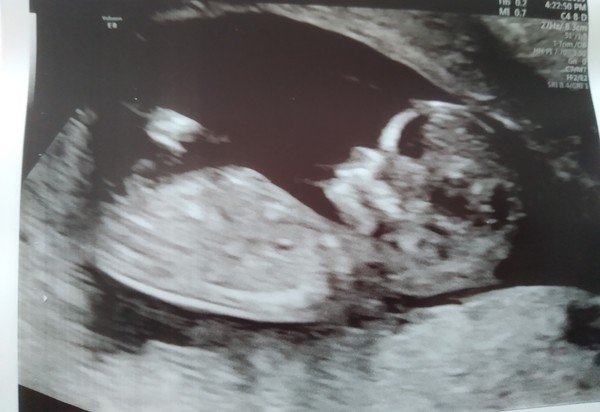

My scan went well yesterday! I'm having a boy! Despite me not gaining weight he's growing fine, measuring three days ahead and had a strong fast heartbeat!

Here he is